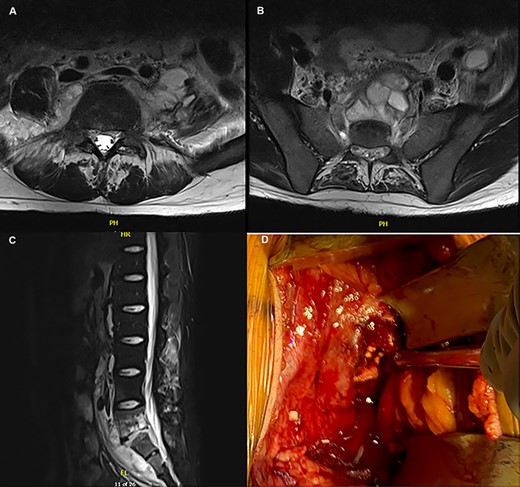

The patient is a 22-year-old previously healthy male who presented to the Emergency Room with a 3-month history of lower back pain elicited after lifting weights at the gym. He also reported intermittent fevers and chills as well as a 20-pound weight loss. He had no recent travel history, worked as a correctional officer and initially denied contact with animals, or consumption of unpasteurized dairy products. On physical exam he had normal vital signs, no spinal or paraspinal tenderness, and no neurologic deficits. A magnetic resonance imaging (MRI) study was notable for findings concerning for discitis/osteomyelitis of L5/S1 with abscess formation (Fig. 1A–C). The patient was admitted and subsequent interventional radiology (IR)-guided biopsies were performed twice, and cultures and pathology were negative for bacteria, fungi and acid-fast bacilli. He was discharged on vancomycin, ceftriaxone and doxycycline for the treatment of osteomyelitis of unknown origin.

(A–C) MRI depicting the osteomyelitis, discitis and abscess involvement around L5/S1; (D) intraoperative picture of the L5/S1 disc space with placement of tobramycin antibiotic beads.